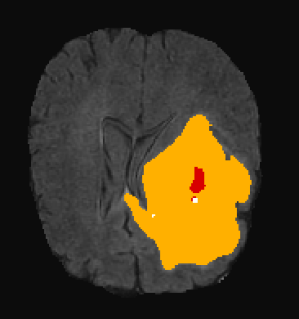

3.3 Visual analysis

Figure 5 shows two subjects among the quantitatively better (first row) and poorer (second row) results. In both cases, it can be visually appreciated that our method correctly segments the whole tumor region. For the subject shown in Figure 5.a, the system is able to properly capture all tumor regions, meaning that the first network is able to correctly localize the tumor and the second network is able to capture differences between tumor regions. On the other hand, in Figure 5.b, we show a case where even though the tumor is correctly localized by the first network, the second isn’t able to properly detect different tumor subregions. We see that edema (ED - label 2) is overrepresented in our segmentation in detriment of smaller classes: GD-enhancing tumor (ET - label 4) and the necrotic and non-enhancing tumor (NCR/NET - label 1). This effect can also be inferred from lower values in ET and TC dice coefficients.